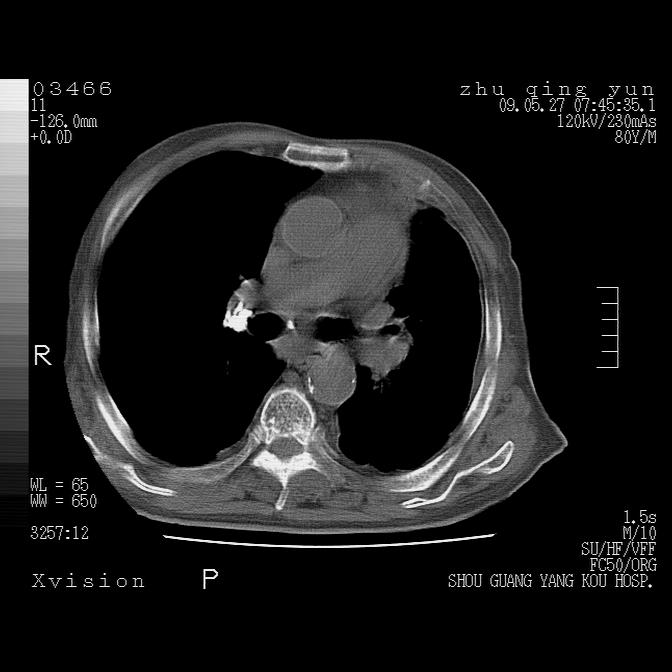

病人男性,年龄80,气喘来院,其他病史不太详细,1月前有过恶心,呕吐,在当地人民医院做过钡餐,诊断胃炎,

后纵隔恶性肿瘤累及心包并纵隔淋巴结转移/左肺癌性淋巴管炎/肺部感染

1)考虑左肺中央型肺癌并阻塞性肺炎,后下纵隔受侵伴纵隔淋巴结转移。2)双侧少量胸腔积液,胸膜增厚。3)心包积液。

左侧中心型肺癌并纵隔淋巴结广泛转移.

恶性占位是肯定的,并累及心包并纵隔淋巴结转移/左肺癌性淋巴管炎/肺部感染。是中心性或纵隔型肺癌,还是后纵隔恶性占位,还是食道中下段癌或食道受累需鉴别。